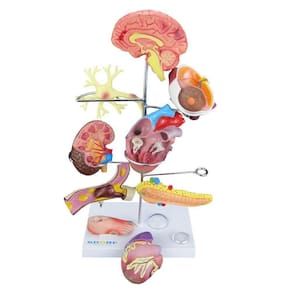

Modelo de Órgãos Afetados pela Diabetes em 11 Partes SD-5213

0 avaliações com média 0 de 5 estrelas.

(0)0 de 5 estrelas

(0)0 de 5 estrelas